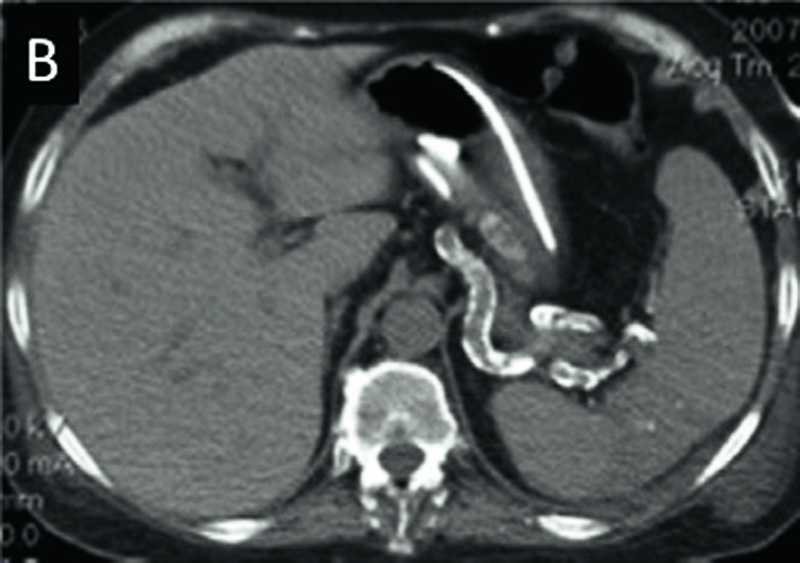

Det finns även fallbeskrivningar (Figur 4) som rapporterar snabbt progredierande kärlförkalkningar hos njursjuka patienter som påbörjar warfarinbehandling [41]. I en aktuell studie visar Schurgers et al [42] att patienter som behandlas med warfarin har signifikant mer förkalkade koronarplack än patienter (matchade för ålder och Fram-inghamrisk-fak-torer) utan sådan behandling. I denna studie rapporterades även att tio veckors warfarinbehandling av aterosklerosbenägna s k ApoE(–/–)-möss förändrade morfologin i de aterosklerotiska placken och ökade deras vulnerabilitet [42].

Figur 4 A. Datortomografi av buk på samma patient med endast nio månaders mellanrum.

Figur 4 B. Efter warfarinbehandling finner man uttalade kärlförkalkningar. Del av bild reproducerad från Hristova et al, 2010 [41].